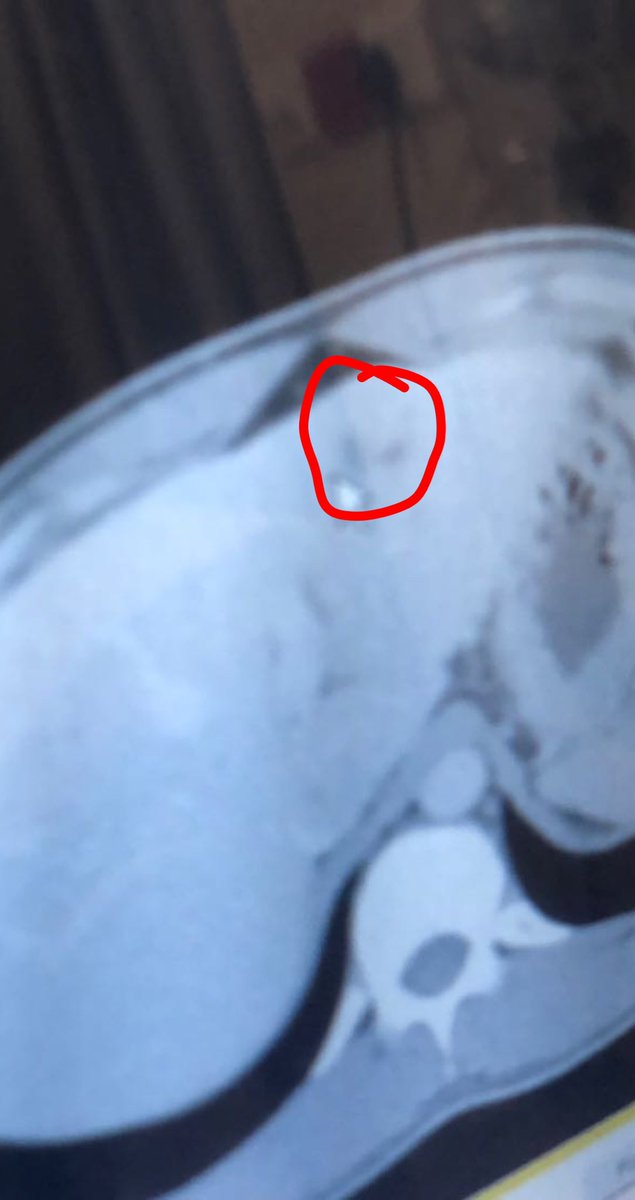

ولكن الصدمه كانت ليلة عمليتي ، طلبوا مني المستشفى كإجراء اعتيادي اشعه اخيره ليلة العمليه ، وكانت المفاجئه والصدمه ان اكتشفوا ليلة العمليه بوجود سرطان بكبدي زي ماهو مبين لكم بالصوره!!!

والله وقتها انصدمت وانهبلت وشلون كذا ، لي 6 شهور افحص واموري تمام وليلة العمليه بالاشعه الاخيره يحصلون الورم وكان على بدايته !!